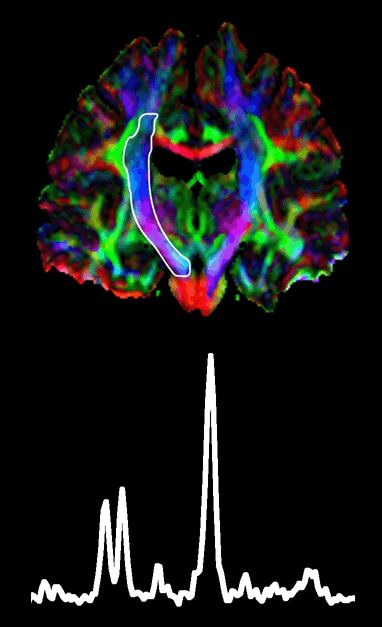

Dr. Sanjay Kalra

Department of Biomedical Engineering, University of Alberta

Areas of research:Amyotrophic Lateral Sclerosis (ALS)